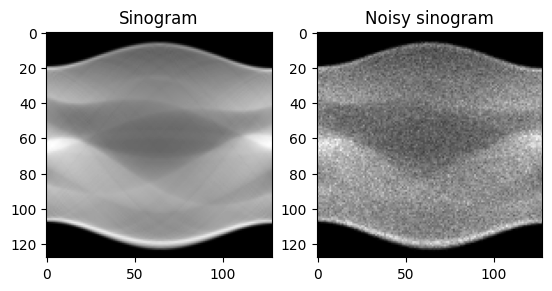

可視化してみると、こんな感じになる。